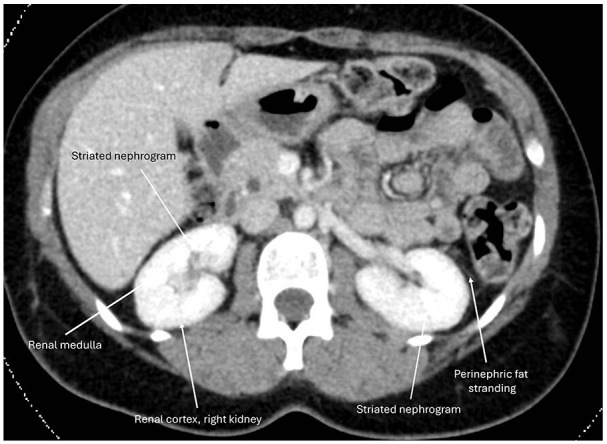

Abstract Image